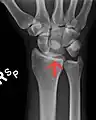

Left hand anterior view (palmar view). Lunate bone shown in red.

The lunate bone (semilunar bone) is a carpal bone in the human hand. It is distinguished by its deep concavity and crescentic outline. It is situated in the center of the proximal row carpal bones, which lie between the ulna and radius and the hand. The lunate carpal bone is situated between the lateral scaphoid bone and medial triquetral bone.

The lunate is a crescent-shaped carpal bone found within the hand. The lunate is found within the proximal row of carpal bones. Proximally, it abuts the radius. Laterally, it articulates with the scaphoid bone, medially with the triquetral bone, and distally with the capitate bone. The lunate also articulates on its distal and medial surface with the hamate bone.[2]:708[3]

The proximal surface of the lunate bone is smooth and convex, articulating with the radius. The lateral surface is flat and narrow, with a crescentic facet for articulation with the scaphoid bone. The medial surface possesses a smooth and quadrilateral facet for articulation with the triquetral bone. The palmar surface is rough, as is the dorsal surface. The dorsal surface is broad and rounded. The distal surface of the bone is deep and concave.[4]